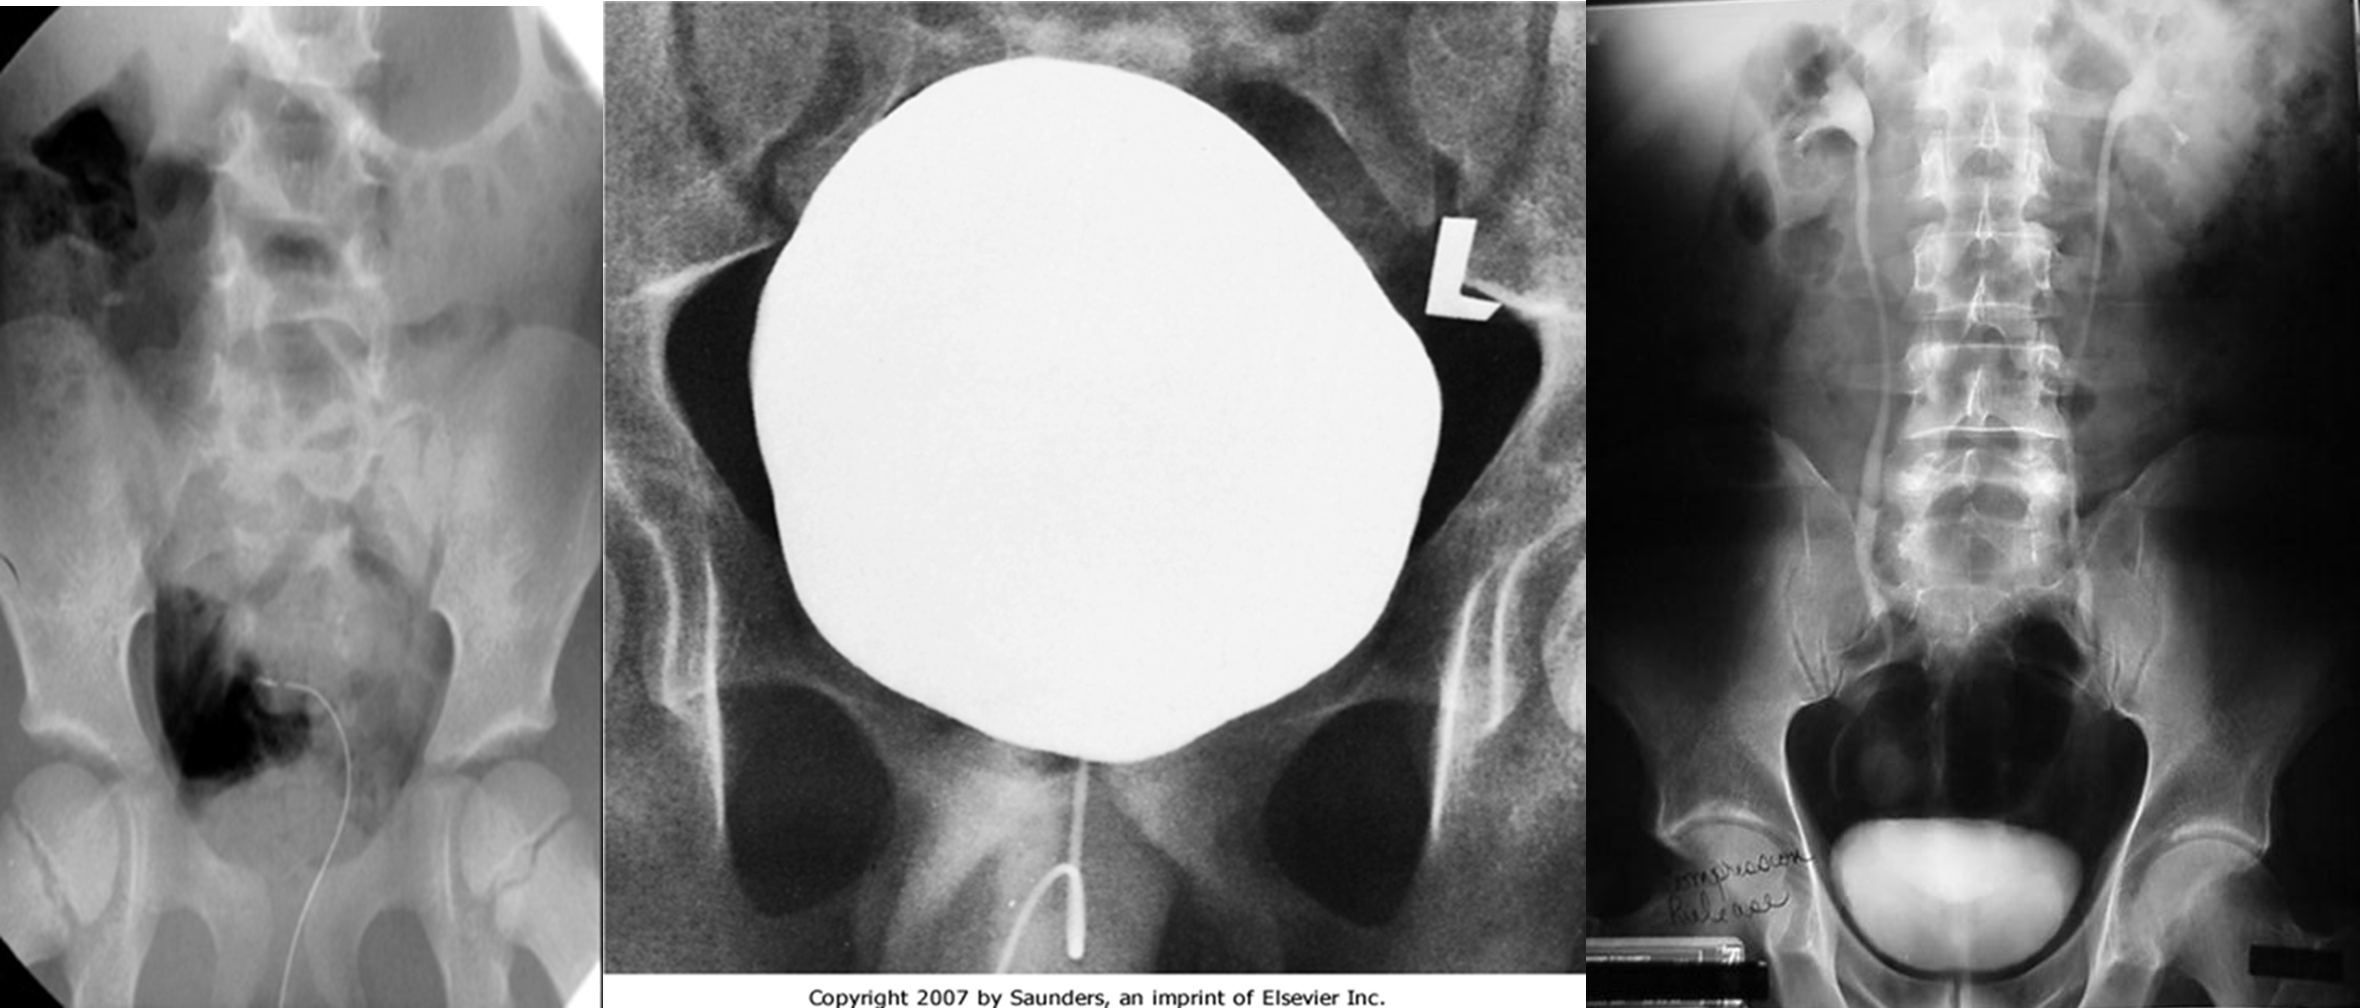

Cystogram

Indications - Cystitis - Trauma - Tumors - Congenital anomalies

Two route of filling the bladder

As part of IVU

- Catheterization and filling the bladder with contrast Cystogram